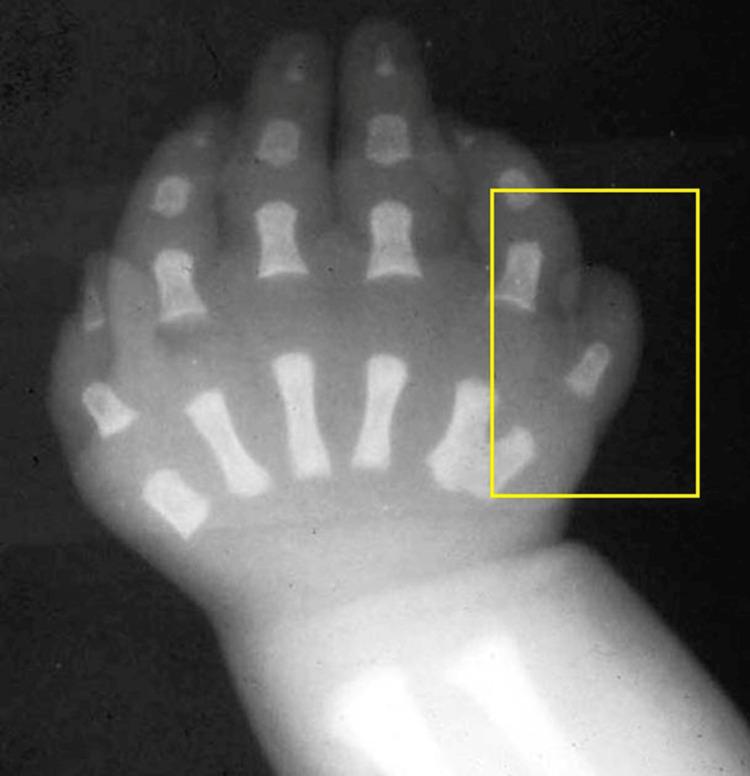

Polydactyly is a common occurrence, observed as the presence of extra digit/s in the hands and feet. It can be categorized into preaxial, postaxial, and mesoaxial forms based on the location of the additional digit. In most instances only a single extra digit is present, research reports with more than one extra digit have been published. Most common management includes surgical excision under the influence of general anesthesia. An alternative approach by removing the pre-axial and post-axial supernumerary digit is carried out under local anesthesia in infants and small children, providing the additional benefit of fewer post-procedural complications. This is a case of a 5-month-old male child, with post-axial polydactyly of the left hand. He was managed by excision of the extra digit under the influence of local anesthesia. The patient recovered well and was discharged 3 days after the procedure with the advice of monthly follow-up until 3 months.

摘要